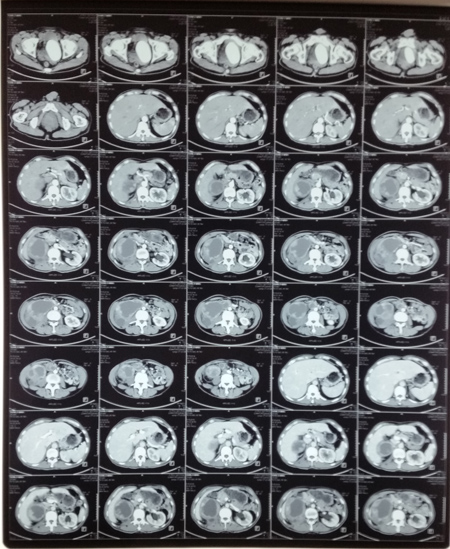

CT增强扫描示右肾、右输尿管多发性肿瘤

日前,泌尿外科王金根主任医师为一位罕见的肾、输尿管、膀胱多发性肿瘤患者成功实施了切除手术,一次性完整切除右肾、右输尿管和全膀胱,术后没有并发症,病理切片证实为腺癌,各切缘均未见癌细胞(表明切除彻底),患者顺利康复出院。患者是一位54岁男性,因反复肉眼血尿2年余,右侧腰痛2月余入院。入院后经相关检查很快确诊了病情:右侧肾盂肾盏、右输尿管全长和膀胱内均生长了大量肿瘤,同时合并感染发烧,膀胱内还有一个巨大结石,此外还存在严重贫血和营养不良,全身水肿。手术切除是患者目前唯一的治疗选择。由于长期梗阻,右侧肾盂肾盏和输尿管重度扩张,加上近期合并感染,肾脏周围广泛粘连,手术分离过程中肾脏及输尿管壁极易破损,一旦破损将会导致肿瘤扩散,严重影响疗效。因此手术难度极大,风险很高,对手术医生的技术要求非常高。王金根博士组织全科专家反复讨论制定治疗方案,并亲自带领治疗组进行充分细致的术前准备。2014年6月9日,由王博士主刀,在全麻下为患者施行了手术。手术中发现患者右肾体积巨大,与腰背部肌肉、肝脏、结肠和下腔静脉等重要器官广泛紧密粘连,手术难度比术前估计的还要大。为了解除患者的病痛,挽救患者的生命,王金根博士、贾灵华硕士和包佑根医生等组成的手术小组迎难而上,历经八个小时的艰苦努力,终于将患者的右肾、输尿管和膀胱完整切除,邻近器官完好无损。